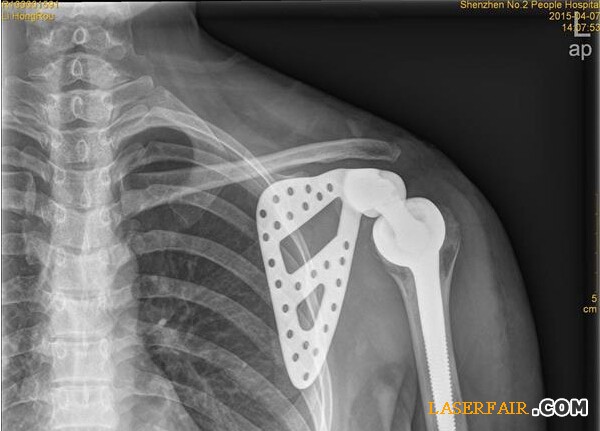

近日,深圳市第二人民醫(yī)院收治了一位27歲女患者,該患者肩胛部位的骨頭已經(jīng)被腫瘤侵蝕四分之三,亟需手術(shù)切除。但是如果貿(mào)然切掉整個肩關(guān)節(jié),不僅手術(shù)風(fēng)險大,恢復(fù)后病人生活也難以自理。于是該院利用3D打印技術(shù)制備出與患者肩胛骨完全匹配的鈦合金假體,置換掉原來腫瘤壞死的肩胛骨,打造了一個新的“肩膀”。

隨著3D技術(shù)的日臻成熟,該醫(yī)院與3D打印公司展開治療研究,針對李女士的治療首次采用3D打印技術(shù)制備出與患者肩胛骨完全一致的鈦合金假體,并成功植入骨腫瘤患者體內(nèi)。

“首先是3D打印人工制作肩胛骨模型,把采集到的李女士左邊肩胛骨大小、形狀等數(shù)據(jù)通過3D技術(shù)打印出完全吻合的模型。”深圳市第二人民醫(yī)院骨關(guān)節(jié)、骨腫瘤科副主任醫(yī)師譚紀(jì)鋒介紹,然后根據(jù)模型設(shè)計出手術(shù)方案,在模型上標(biāo)注手術(shù)的螺釘孔、切除邊界,實現(xiàn)手術(shù)精準(zhǔn)化。”由于3D模型采用的樹脂材料不能直接植入人體內(nèi),因此醫(yī)院將模型送至人工關(guān)節(jié)制作廠,制作出鈦合金人工肩胛骨。在為李女士進行腫瘤完整切除后,再將鈦合金人工肩胛骨植入患者體內(nèi)。由于3D打印實現(xiàn)了“量體裁衣”,因而鈦合金人工肩胛骨能實現(xiàn)精準(zhǔn)匹配。

14日,記者從醫(yī)院獲悉,李女士的手術(shù)很成功,很快就可以出院了。據(jù)了解,這是深圳乃至華南地區(qū)首例肩胛骨3D打印鈦合金假體植入術(shù)。

據(jù)悉,人工定制關(guān)節(jié)手術(shù)醫(yī)療花費在10萬元左右。譚紀(jì)鋒透露,李女士做完置換手術(shù)后,身體狀況良好,一兩天后即可出院,半年后,可完全恢復(fù)生活自理。